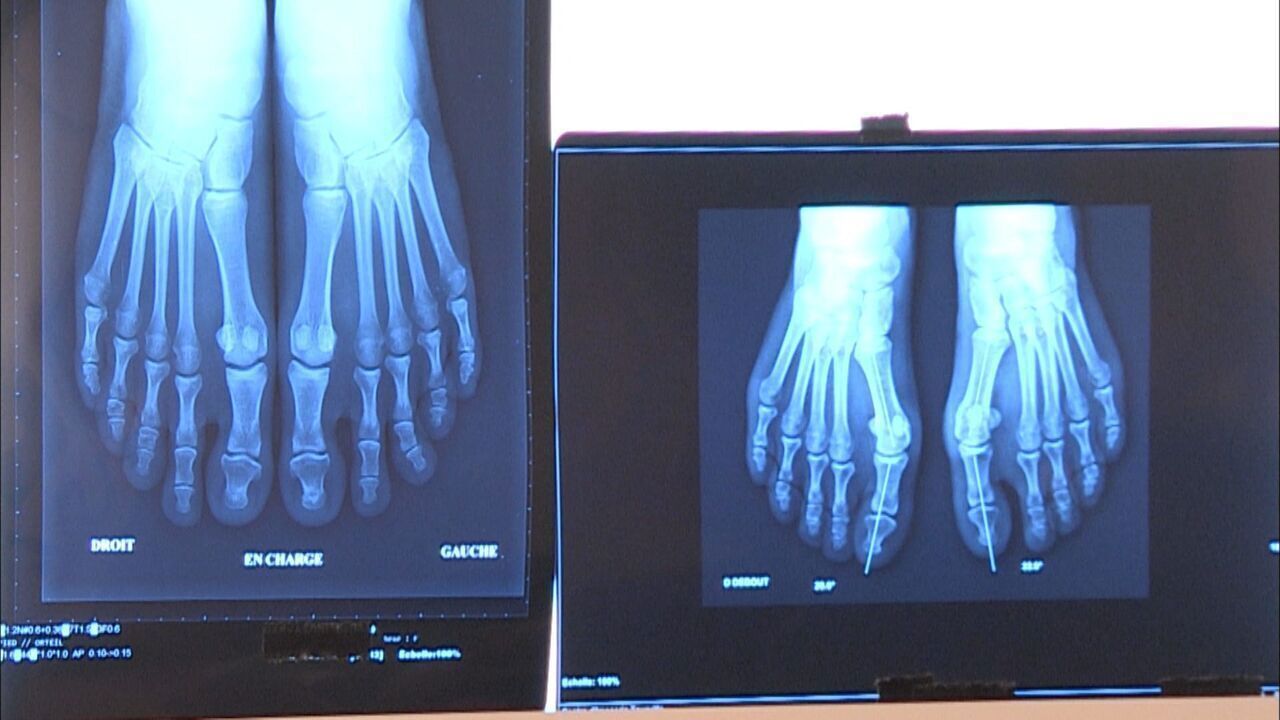

Hallux valgus: je operacija res nujno potrebna?